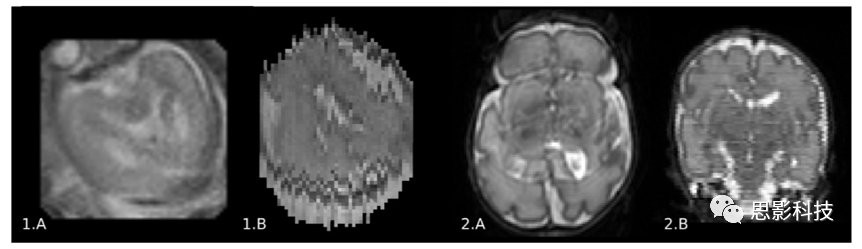

a) 與成年人相比,嬰兒腦MRI運動偽影的發(fā)生率更高。胎兒和未鎮(zhèn)靜的新生兒表現(xiàn)出明顯的運動,這就需要采用更快的采集技術(shù)或多次采集大腦影像來校正運動。運動偽像表現(xiàn)為未對齊的圖像切片和沿相位編碼方向的重影(ghosting effects)現(xiàn)象(如圖2所示)。

2所示。胎兒(1)和新生兒(2T2 MR圖像上的運動偽影。在相位編碼方向切片的模糊和重影效應(yīng)(1.A,2.A)以及切片沿方向的錯位(1.B,2.B)表明了明顯的運動。